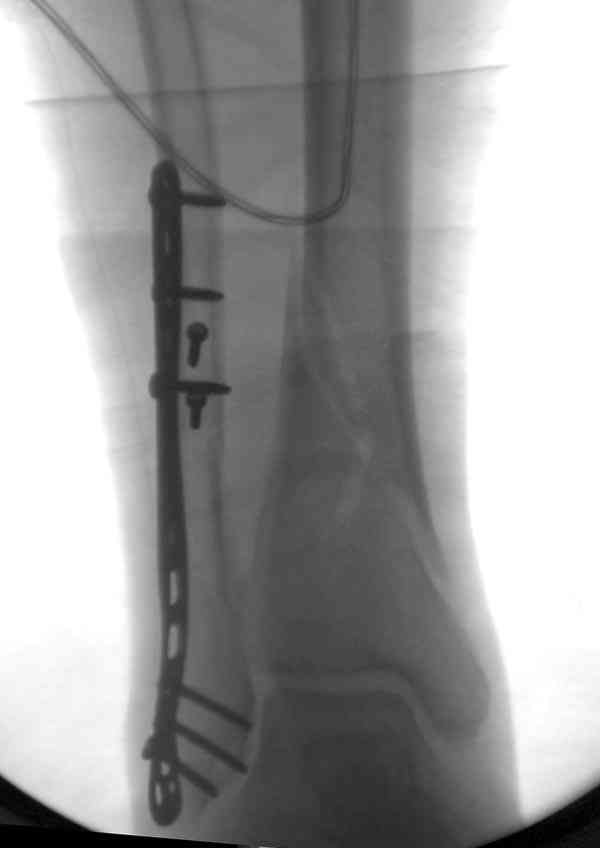

Вторая пациентка 34 лет, перелом получала в Испании, где от операции отказалась, дома по приезду сняла скотчкаст и лечилась у костоправов, нагрузка с 3 недели. Операция через 3 мес после травмы. Остеотомия м-б кости, фиксация пластиной, восстановление МБС. Так как медиальная лодыжка подтянулась, суставная щель на ЭОП контроле нормализовалась ограничились латеральным доступом. Реконструкцию заднего края не пытались сделать тк там уже прослеживалась консолидация, а сминать эпиметафиз не хотелось. В настоящее время ходит с тростью \три месяца после операции\, сустав нестабилен-слабость дельтовидной связки. Супинатор и плотные кроссовки дают возможность длительно ходить. Первый снимок сделан в Испании после репозиции, второй через 2 месяца после травмы перед операцией, третий-через 3 мес после операции.

Глубокоуважаемый Антон, мне кажется в обоих наблюдениях не была достигнута цель операции: Восстановление длины малоберцовой кости и и фиксация ее в анатомичном положении. Отсюда все последующие проблемы, а не от дельтовидной связки.

Как отметили коллеги, в обоих наблюдениях не были достигнуты цели восстановления, игнорирован основной принцип, длина малоберцовой, без которой всякие попытки обрешены на провал.

По снимкам в первом случае, укорочение малоберцовой приблизительно около 8-10 мм. Удовлетворительным восстановлением длины малоберцовой считается, когда на снимке суставная щель равны со всех сторон.

Несмотря на прошедшее время с момента травмы и попытки восстановления, мы бы рекомендовали повторить процедуру по сохранению сустава. Для этого очищается синдесмоз от фиброза, удлиняется малоберцовая на мортизной ренгенограмме засчет проксимальной поперечной остеотомии вставлением расширящего инструмента (lamina spreader).

Сравнительно свежие (8-12 недельные) случаи удлиняются за счет косых остеотомий, обычно по линии перелома, затем производят фиксацию

синдесмоза. Фиксацию синдесмоза рекомендуем не менее чем двумя паралельными кортикальными шурупами через 3 или 4 кортикальные слоя.

Латеральная пластина усилит конструкцию.